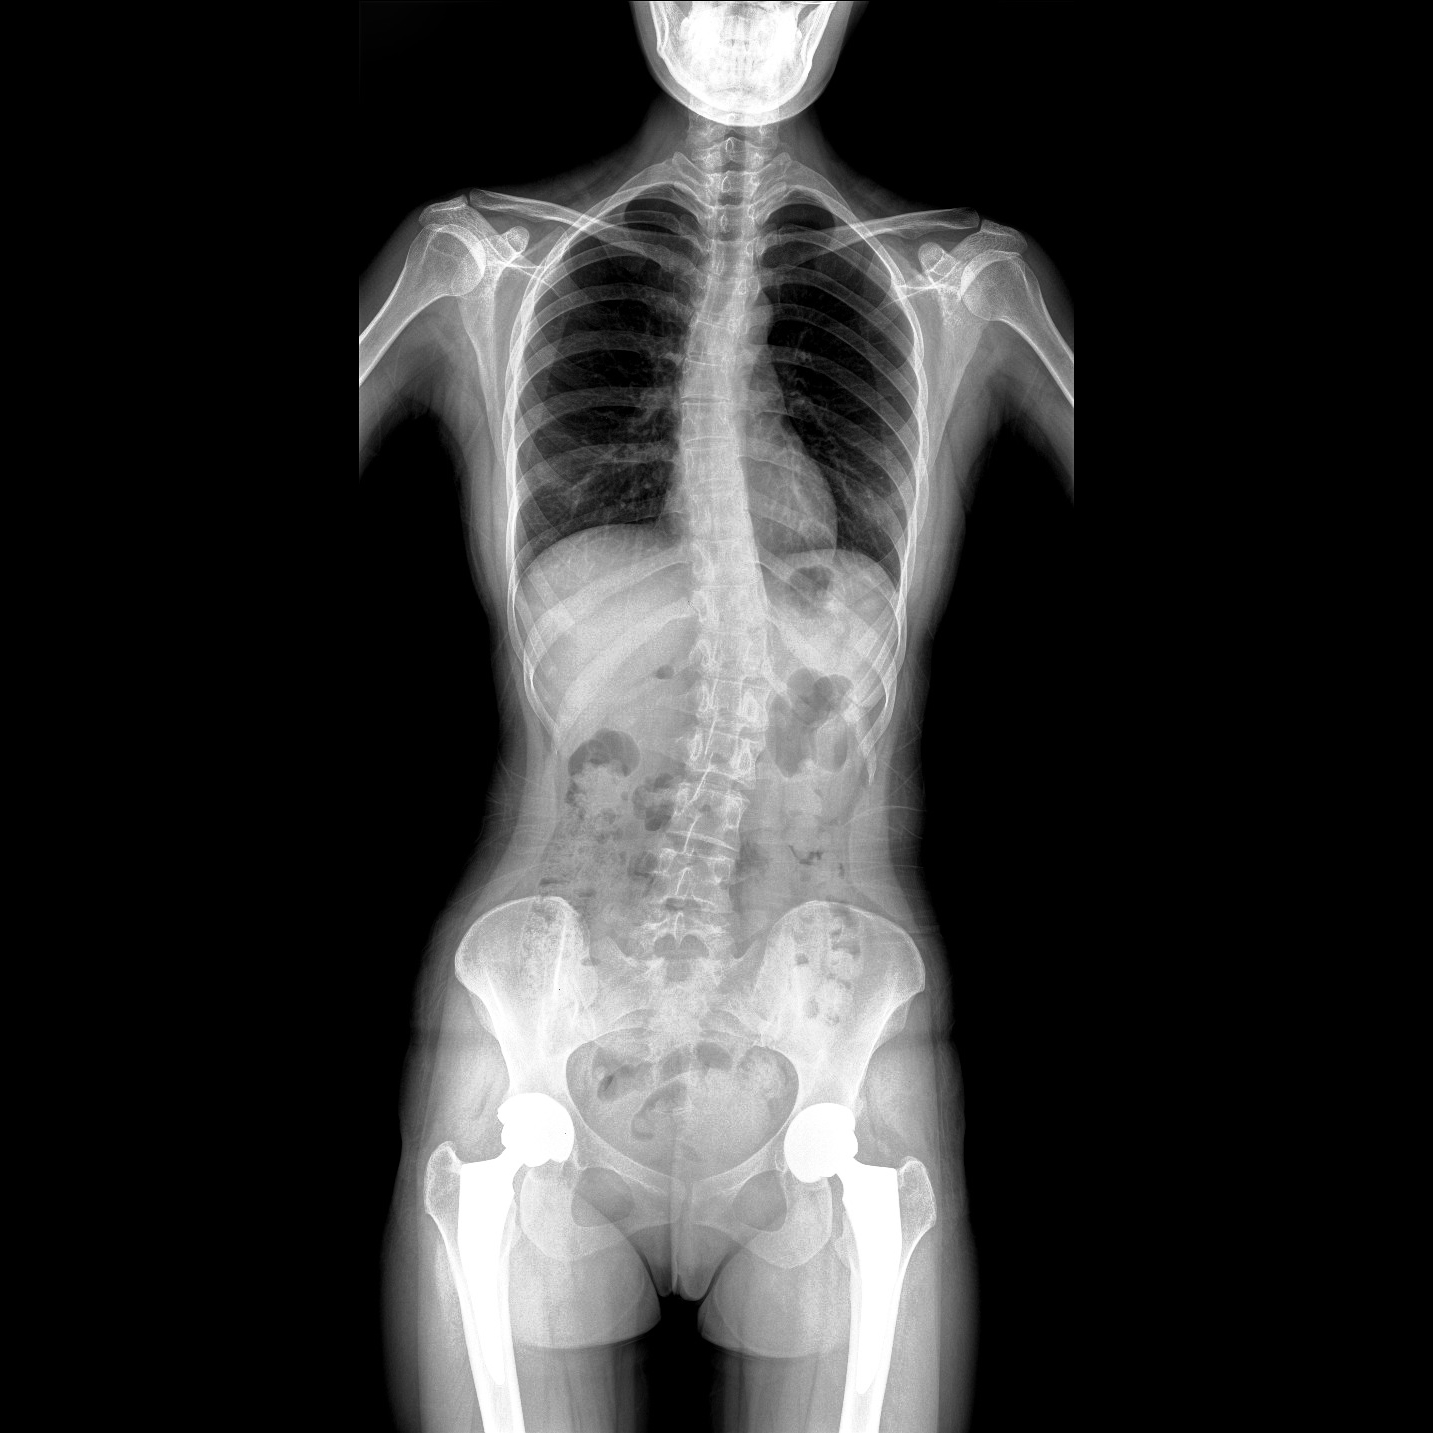

支持全脊柱攝影、雙下肢攝影、脊髓造影、復雜創(chuàng)傷、人工關(guān)節(jié)置換、關(guān)節(jié)損傷的修復重建等大視野臨床應用

17"*34"有效視野,一次成像不拼接。相較于多張攝影再軟件拼接的DR設備,PLX8600解決了拼接圖像存在密度不均勻,拼接處圖像配準和放大效應等問題,給臨床帶來了大視野影像解決方案,可一次性覆蓋全脊柱或雙下肢影像。